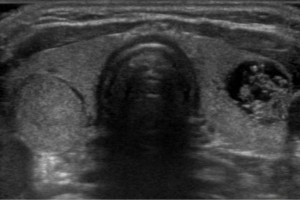

Diplomados en Ultrasonografía